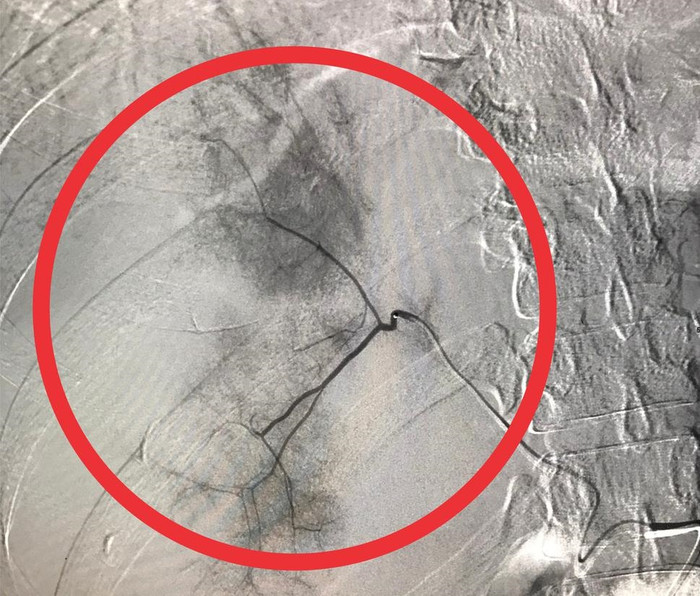

Ảnh chụp CT-scan cho thấy gan phải bị vỡ. (Ảnh: BVCC).

Đến rạng sáng 20/2, chị L. bất ngờ bị đau bụng dữ dội nên được người nhà đưa đến bệnh viện để điều trị. Qua thăm khám, bác sĩ chẩn đoán chị L. bị dập vỡ gan phải hạ phân thùy V, chảy máu ổ bụng, gây xuất huyết nội rất nguy hiểm.